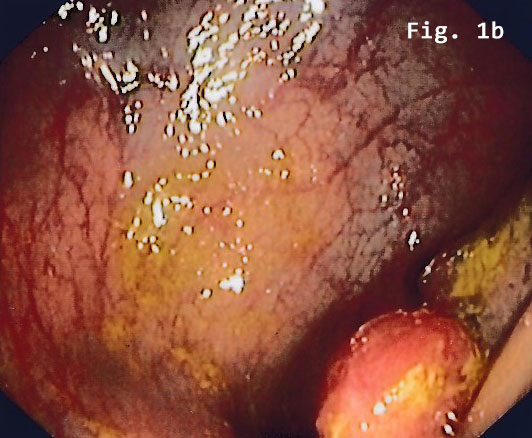

Colonoscopy revealed a semi-circular polypoid lesion in the sigmoid colon suggesting malig-nancy [Figure 1].

![Endometriosis infiltrating the sigmoid colon</br> [May 2017]](http://s834315022.websitehome.co.uk/wp-content/uploads/2020/11/cotm_may2017_fig1a.jpg)

![Endometriosis infiltrating the sigmoid colon</br> [May 2017]](http://s834315022.websitehome.co.uk/wp-content/uploads/2020/11/cotm_may2017_fig1b.jpg)